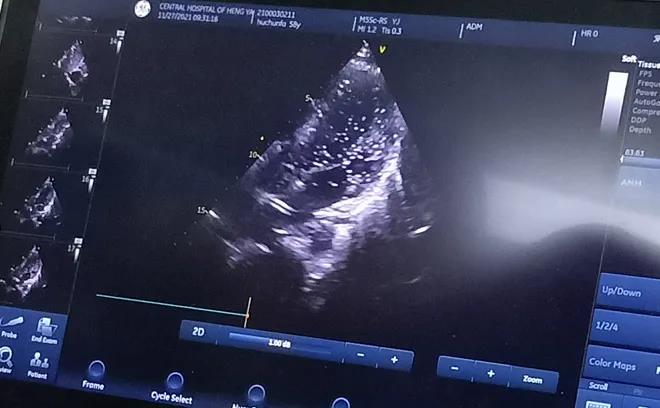

經(jīng)充分的術(shù)前準備后, 11月27日上午,胡先生接受局部麻醉下經(jīng)皮介入PFO封堵術(shù),手術(shù)全程病人清醒,醫(yī)生一邊與胡先生交流,一邊進行手術(shù),術(shù)后無傷口創(chuàng)面?;颊弋?dāng)天即下床活動,復(fù)查心臟彩超提示封堵器位置良好。

胸超聲心動圖引導(dǎo)下經(jīng)股靜脈房間隔缺損封堵術(shù)是在胸超聲心動圖實時監(jiān)測下的封堵術(shù),與傳統(tǒng)開胸行房間隔缺損修補術(shù)相比,只需要通過大腿股靜脈進行穿刺便可完成,出血少、不縫針,真正做到了“微創(chuàng)”,創(chuàng)傷小且不影響美觀;與內(nèi)科介入下手術(shù)相比,又避免了X線對患者的放射損傷。在胸超聲實時引導(dǎo)下操作,定位準確,隨時可調(diào)整封堵傘位置,適合于繼發(fā)孔房間隔缺損、室間隔缺損、動脈導(dǎo)管未閉等各種常見先天性心臟病的治療,對先心病心臟病患者的治療又提供了一項新的微創(chuàng)治療方法。該技術(shù)因創(chuàng)傷小、恢復(fù)快,術(shù)后3至5天即可出院。